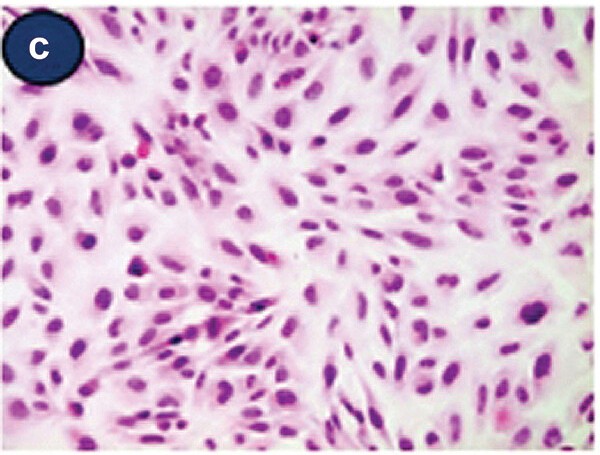

Fig. 1. Light micrographic findings of attached Beas-2B cells (H&E staining) (Lee, Y. and Ryu, Y. J., 2023).

BEAS-2B cells are a widely utilized immortalized, non-tumorigenic human cell line, established in 1988 from a bronchial epithelial biopsy of a healthy male, lacking cancerous pathology. This cell line was immortalised by infection and cloning with the adenovirus 12-SV40 hybrid virus while maintaining the potential to differentiate into squamous tissue when exposed to serum. BEAS-2B cells also encode many lung epithelial cell markers, including cytokeratin, E-cadherin and alpha-smooth muscle actin (α-SMA). BEAS-2B cells in serum-free medium have the typical polygonal shape of respiratory epithelial cells, while those in serum-rich media become more fibroblastic at lower cell counts.